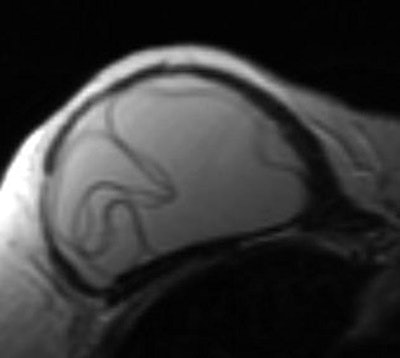

Linguine: After implantation of a silicone or saline breast implant, a fibrous capsule or scar forms around the implant shell. In an intracapsular rupture, the contents of the implant are contained by the fibrous scar, while the shell appears in a group of wavy lines. The linguine sign is most commonly picked up on MRI, and the same findings are seen on CT in patients with bilateral ruptured saline implants.